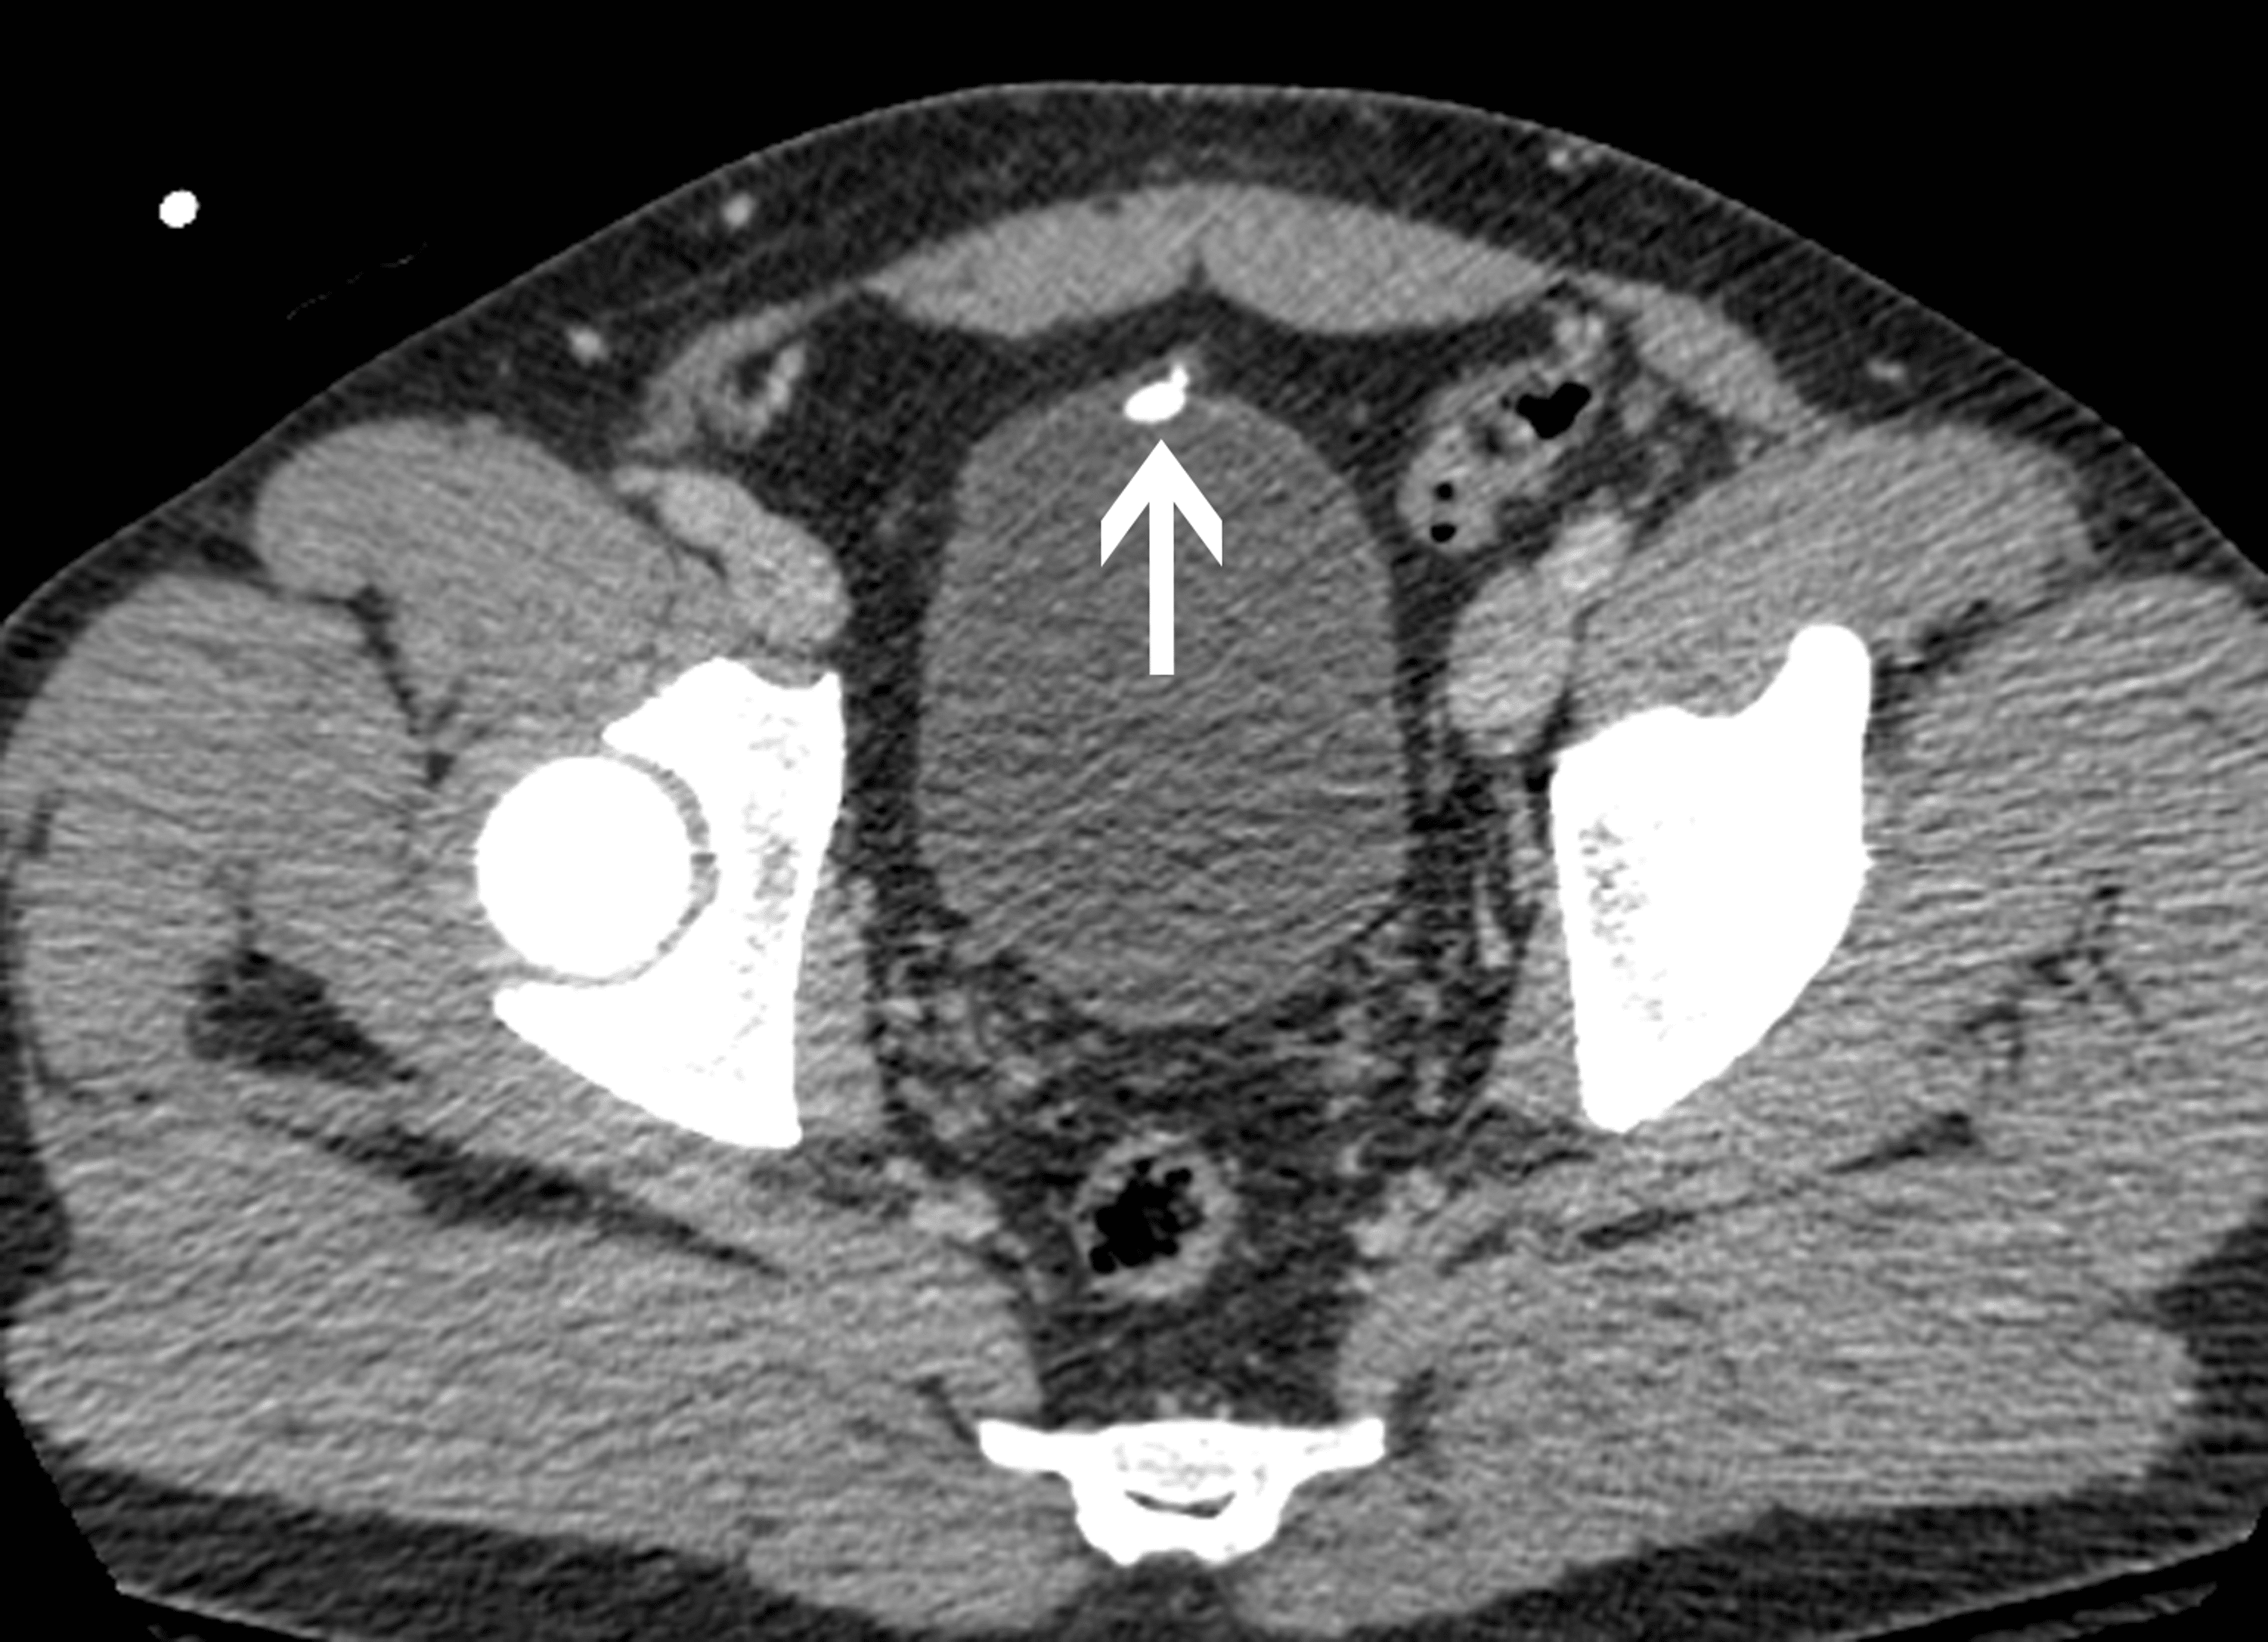

From www.ctisus.com

Large Bladder Stone and Chronic Cystitis Genitourinary Case Studies Crushing Of Stone In The Bladder Bladder stones—also known as bladder calculi, vesical calculi, or cystoliths—are hardened. They develop when the minerals in concentrated urine crystallize and. Bladder stones are hard masses of minerals in your bladder. Surgery is usually needed to remove the stones from the bladder. Is it possible my bladder stones could pass without treatment? A cystolitholapaxy is a surgical procedure that treats. Crushing Of Stone In The Bladder.